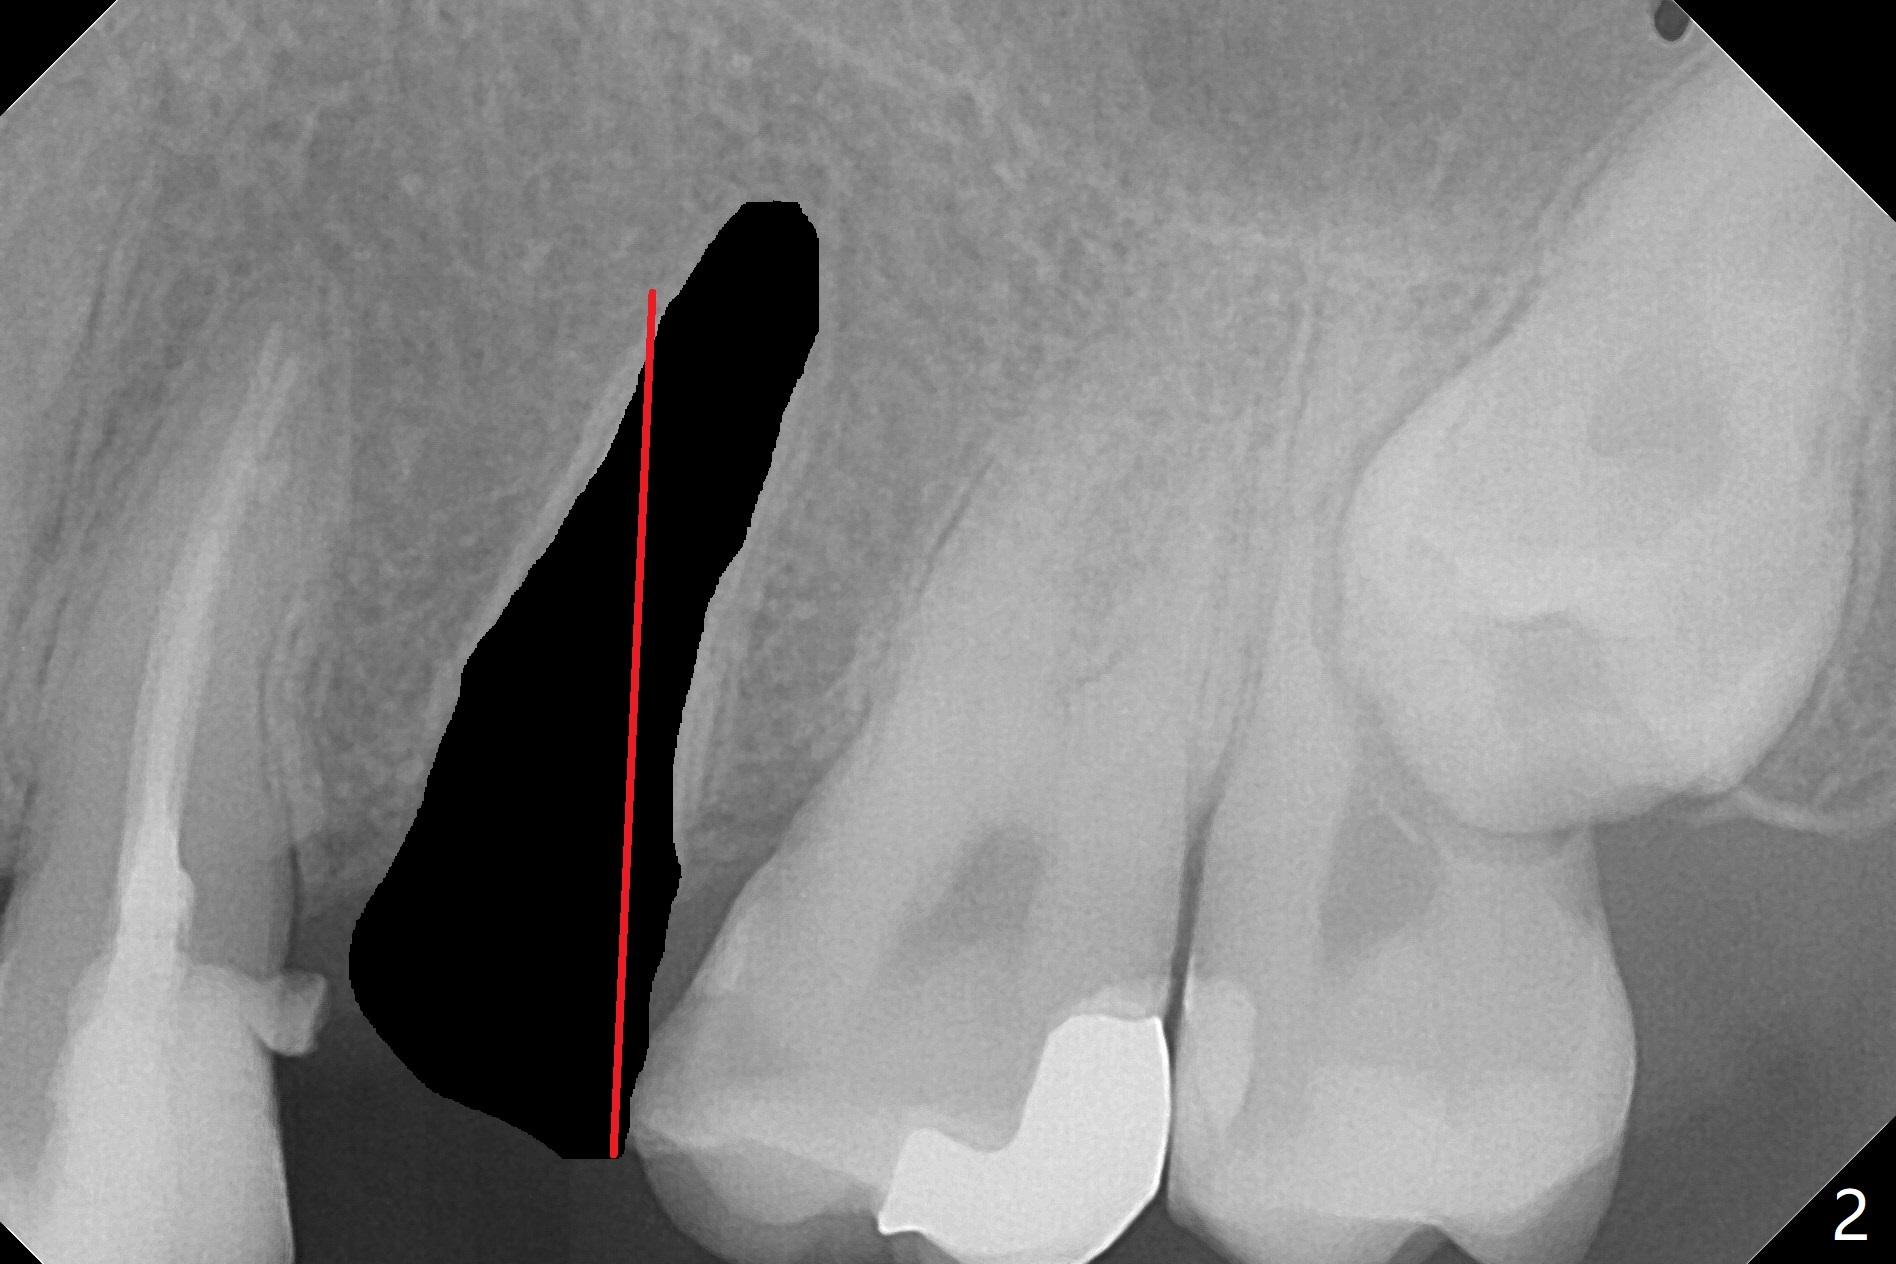

A 27-year-old man returns to clinic with #13 subgingival fracture, which is associated with Class III malocclusion and anterior open bite (Fig.1). Both #1 and 16 seem to be buccal to the 2nd molars, causing root resorption (Fig.1 *). Since the root of the 2nd premolar tilts distal, osteotomy for an implant will be in the mesiopalatal aspect of the extraction socket (Fig.2,3 red). Following implant placement, #16 will be extracted (Fig.3 black), laying foundation to distalize and intrude #14 and 15 to make space for #13 implant crown and reduce anterior open bite and posterior tooth overloading (Fig.4 arrow). No Deviation Clindamycin Xin Wei, DDS, PhD, MS 1st edition 08/25/2020, last revision 09/08/2020